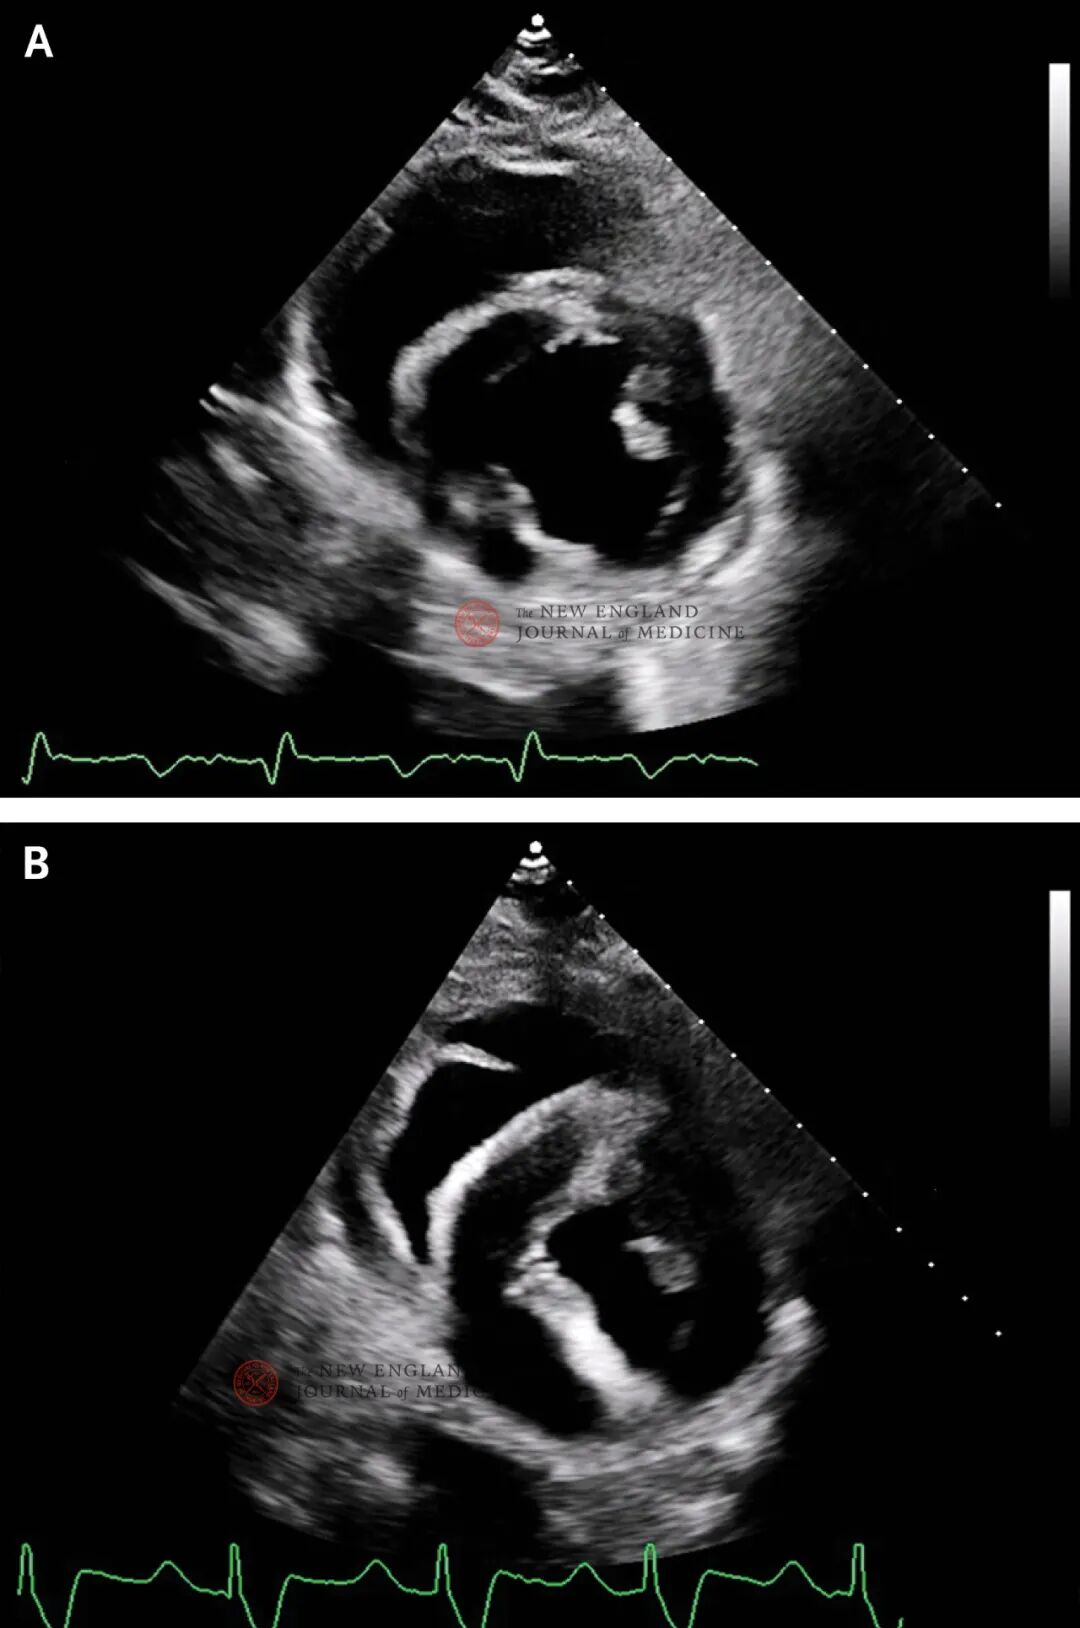

LVEF在术后保持正常或高动力状态(图2和3B)。然而,左心室和右心室壁厚度、左心室腔大小和整体纵向应变发生变化。从移植到第45天,沿室间隔和后壁底部测得的左心室壁厚度为1.2~1.4 cm,在短轴视图上测得的右心室壁厚度为1.0~1.1 cm,左心室腔大小为3.4~4.6 cm。整体纵向应变表明基线时顺应性良好,数值范围为−25%~−36%。

图3. 经胸超声心动图。

心内膜心肌活检提示无排斥

移植后第34天,心内膜心肌活检显示并无排斥迹象(图4A),右心房压为5 mmHg,肺动脉压为25/15 mmHg,心脏指数为2.7,混合静脉血氧饱和度为65%。患者可在无需心血管支持的情况下复健,异种移植物功能正常,无排斥迹象(图2A)。

剖腹探查未见异常。新放置的肺动脉导管显示混合静脉血氧饱和度为33%。虽然超声心动图显示LVEF为65%~70%,但左心室壁厚度和右心室壁厚度显著增加,左心室腔显著减小(图2B)。

与基线相比,左心室壁和右心室壁持续增厚,左心室腔持续减小,且与左心室舒张末期容积和负荷无关。整体纵向应变值由负值向0显著变化(即异常加重)(图3B)。

复查超声心动图显示LVEF大于70%,右心室功能正常,纵向应变改善。双心室壁增厚略有减轻,左心室腔仍然减小。在无需儿茶酚胺支持的情况下,患者的静脉-动脉ECMO流量可从每分钟4.5升缓慢减少至每分钟3升。后续超声心动图未显示室壁厚度、心室腔大小或整体纵向应变有所改善,ECMO流量无法减少至每分钟2升以下。